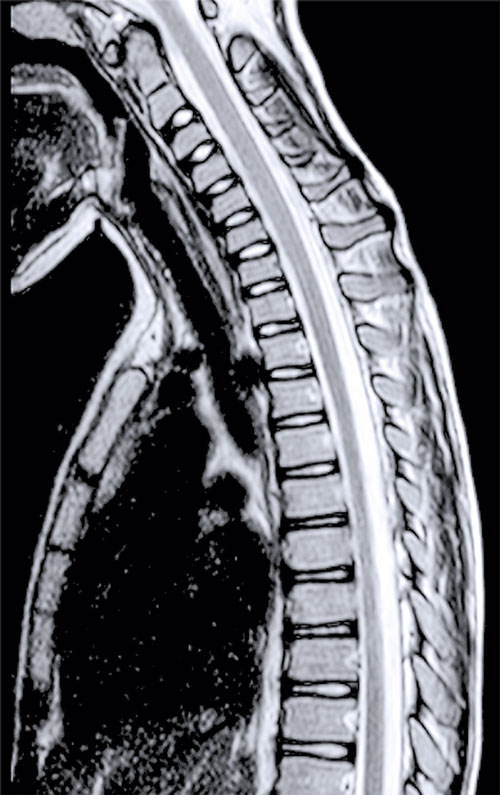

Omfattande mikrobiologisk utredning genomfördes, inklusive prov från likvor, blod, feces m m. Nasofarynxaspirat kontrollerades 10 dagar efter det att han först insjuknat och utföll positivt för enterovirus. Senare typning påvisade EV-D68. MR visade fokala signalförändringar i pons och medulla oblongata samt långsträckta signalförändringar över flera nivåer i ryggmärgens gråa substans utan kontrastmedelsupptag som vid en långsträckt central myelit (Figur 2).

Figur 2 (fall 2). Vid initial MR-undersökning visade T2-viktad sekvens långsträckta signalförändringar i hela ryggmärgen (första bilden) samt fokalt i bakre delen av pons (andra bilden). Axialt i höjd med C2 påvisades engagerad grå substans (tredje bilden). Vid uppföljande MR-undersökning visade T1-viktad sekvens över halsryggmärgen (sista bilden) endast kontrastladdning i nervrötter.